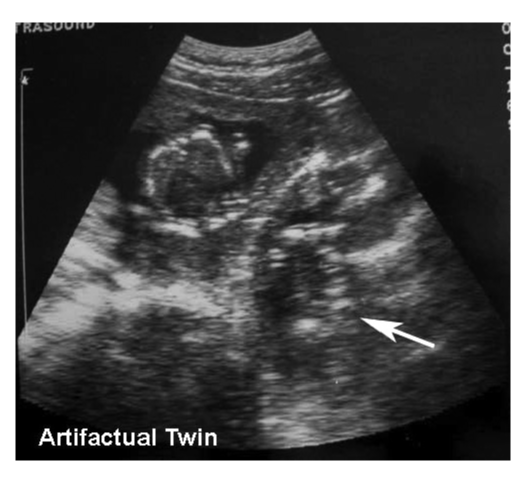

Artifactual twin resulting from refraction through the rectus muscle.

_page_25.png?sfvrsn=6e086e97_2)